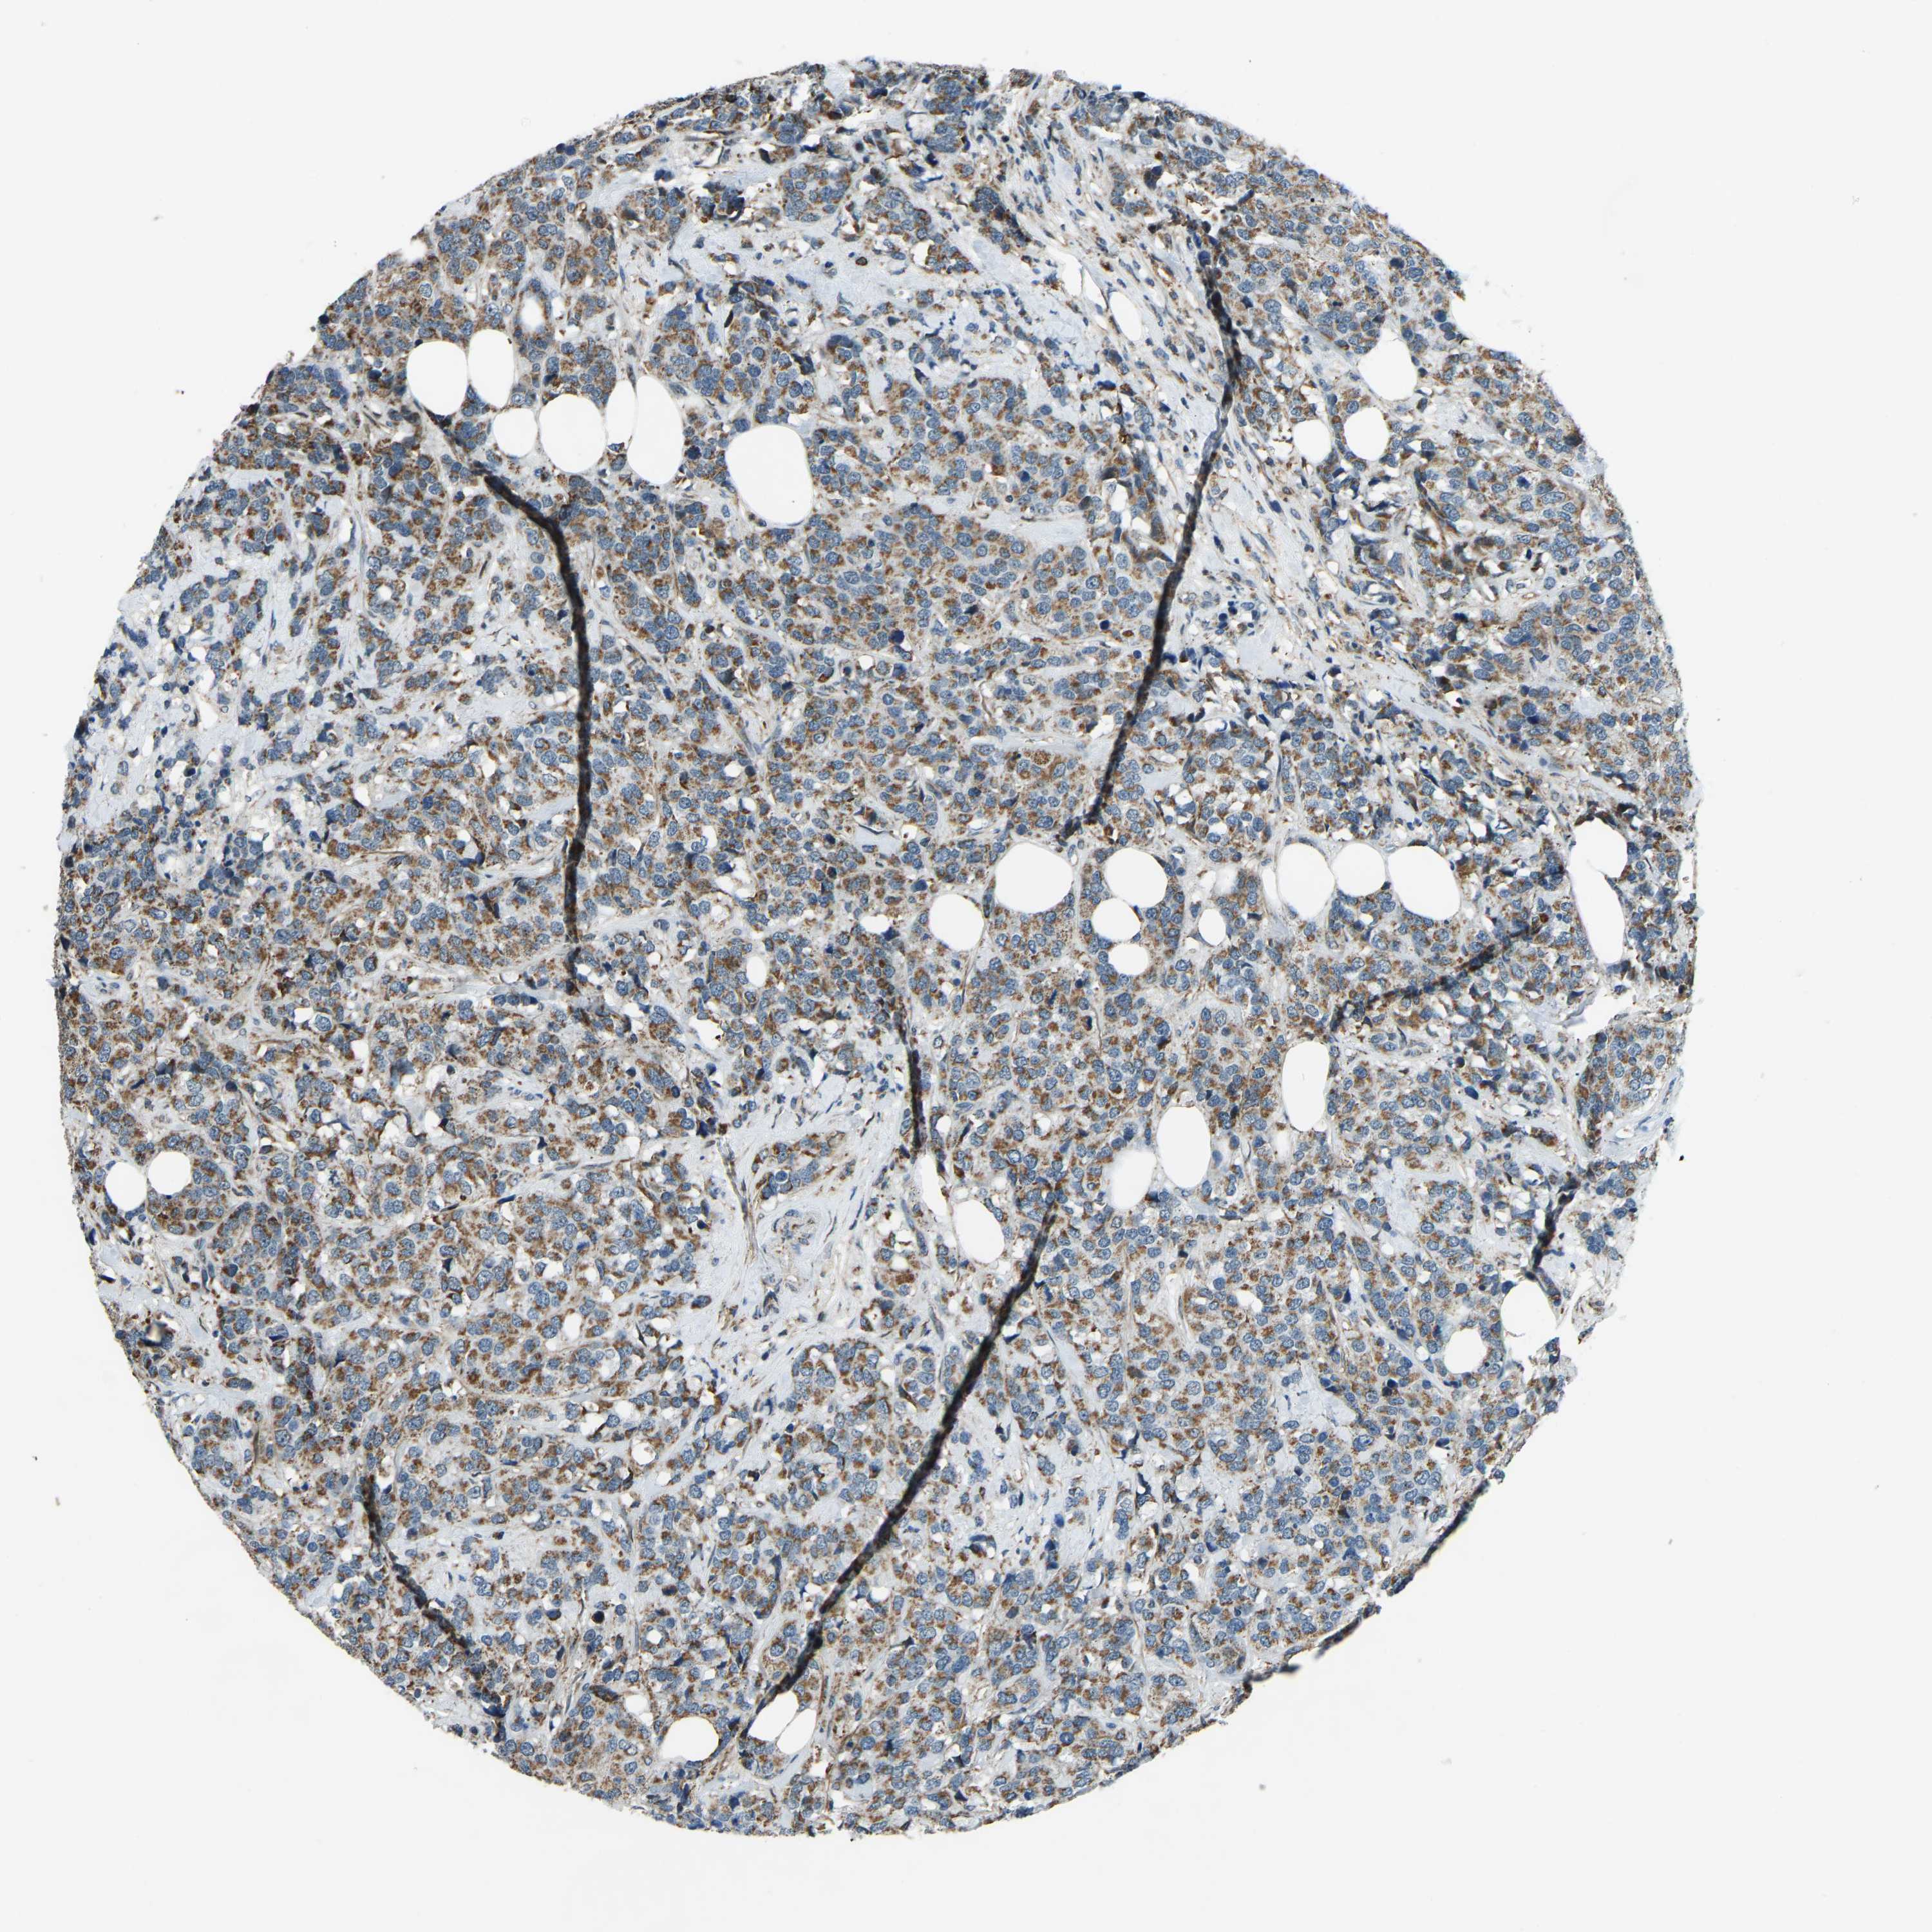

CANCER BREAST CANCER Show tissue menu

BRCA TCGA BRCA VALIDATION PROTEIN EXPRESSION